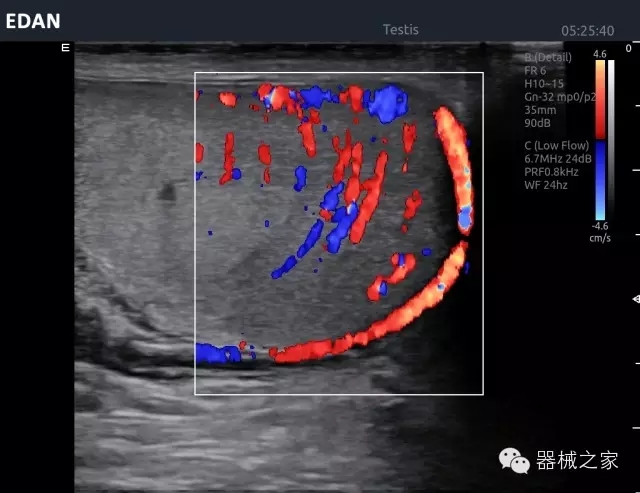

臍帶血流